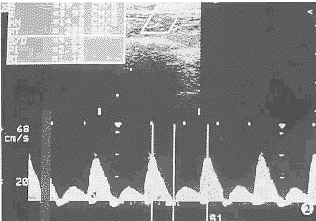

1.正常时:健康犬正常下肢动脉流速曲线为三相波型(图1),频带窄,其下方有明显的缺损,即“窗口”。收缩期加速度较大,波峰陡,迅即达到峰值流速;舒张早期出现反向血流,晚期则为波峰较小的正向血流。

图1 正常犬股动脉流速曲线,三相波型,频带窄,其下方有“窗口”

2.轻度狭窄:股动脉流速曲线仍呈三相波型,但频带稍增宽,反向波减小,加速度下降。

3.中度狭窄:狭窄长度≤2 cm时股动脉流速曲线仍呈三相波型但频带增宽,反向波和加速度进一步减小(图2);狭窄长度为3 cm时波型迥异,89%表现为反向波消失的正向连续波型,频带增宽,其下方的“窗口”消失。

图2 腹主动脉中度狭窄、狭窄长度1 cm时的股动脉流速曲线,反向波减小,频带增宽,PSV、SA、PI及RI均降低

4.重度狭窄:股动脉流速曲线增宽并呈单峰连续波型,反向波和“窗口”消失。随着狭窄长度的增加,加速度进一步减小,呈现Tardus-Parvus现象(图3)。狭窄长度3 cm组有2例表现为静脉样流速曲线(图4)。

图3 腹主动脉重度狭窄时的股动脉流速曲线,呈反向波消失的

单向连续波型,频带宽,PSV、SA、PI及RI明显降低

图4 腹主动脉重度狭窄,狭窄长度为3 cm时的股动脉流速曲线,呈静脉样无搏动,流速较低